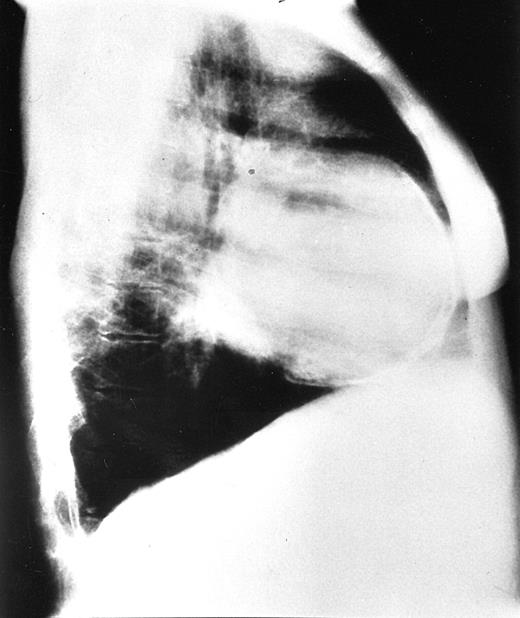

Chest radiographs revealed increased cardiothoracic index levels in 54 (49%) patients. Eighteen (16.3%) had prominent pulmonary arteries. Signs of obvious bone marrow expansion were present in 25 (22.7%) patients and included intrathoracic extramedullary hemopoietic masses in 21 (19%) patients and widening of ribs in 10 (9%) patients (Figure 1). Pericardial calcification was found in a 42-year-old patient with a history of pericarditis but no history of tuberculosis and negative findings on the Mantoux test (Figure 2).

Chest radiograph of a 42-year-old patient.

Lateral view shows pericardial calcification and enlargement of ribs.